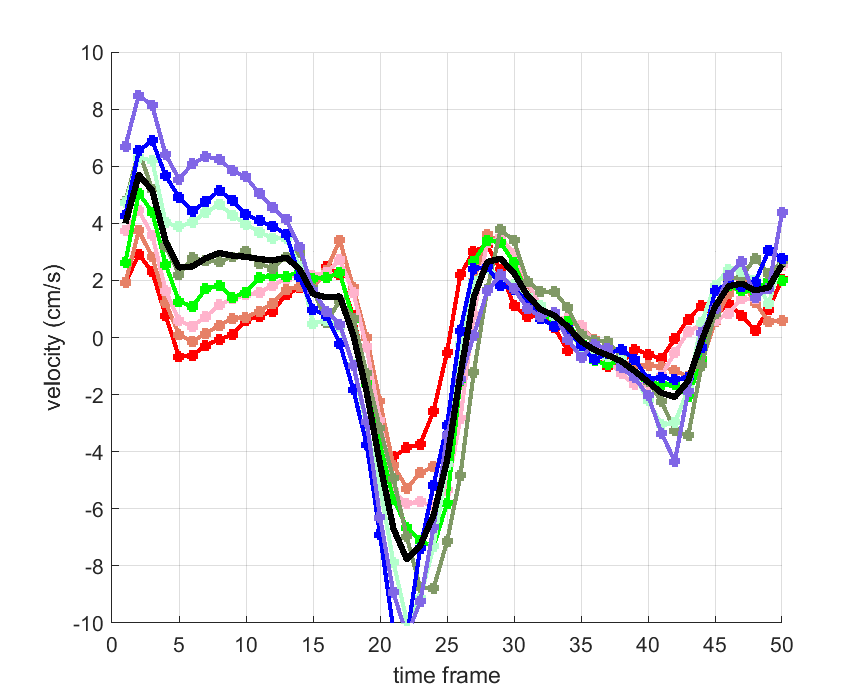

Time courses of the estimated translational component per subject, frame, slice and volume along the 3 velocity directions x, y and z are presented in Fig.6 - Fig.8.